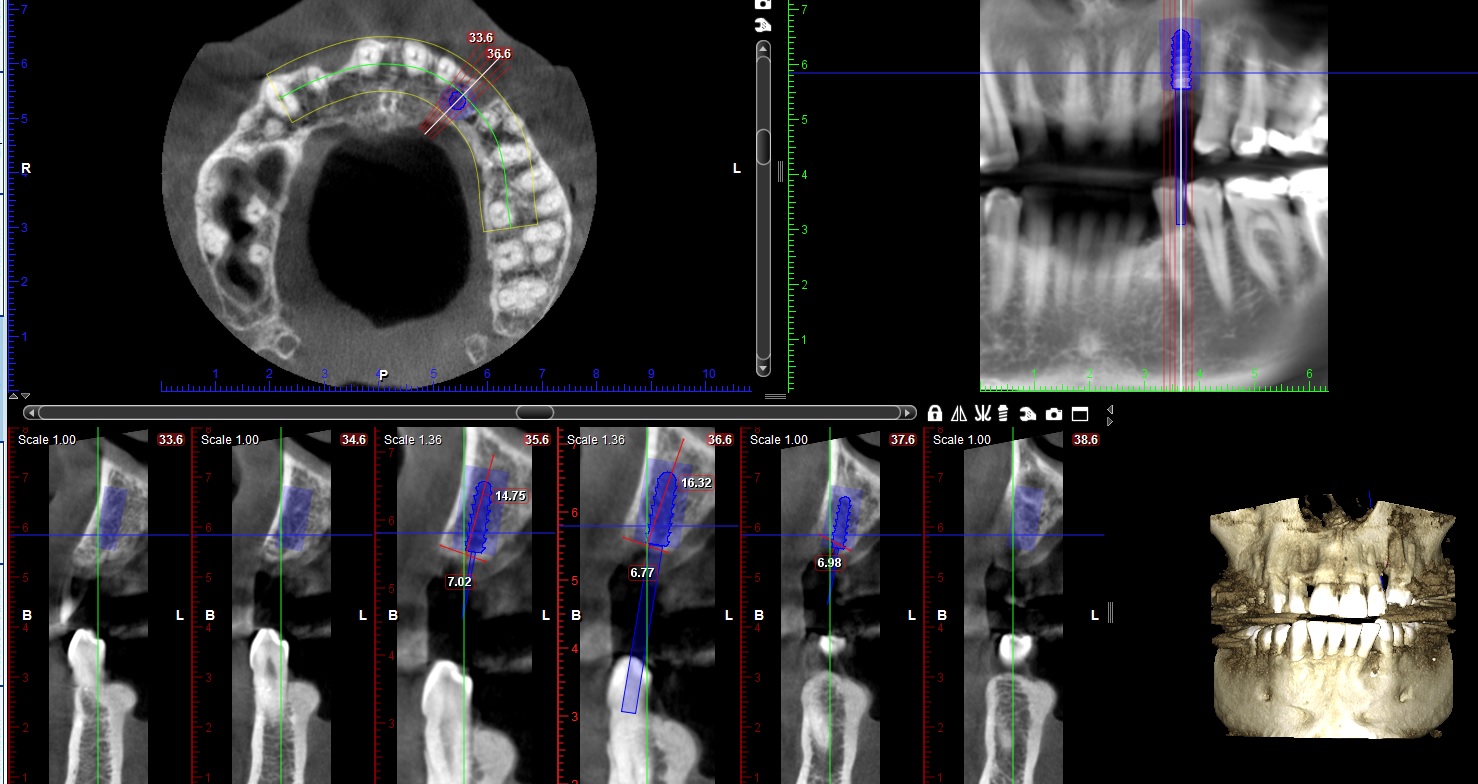

3D-CBCT (ΤΟΜΟΓΡΑΦΙΑ ΚΩΝΙΚΗΣ ΔΕΣΜΗΣ)

Αποτελεί σήμερα την πιο σύγχρονη εξωστοματική απεικονιστική μέθοδο στην ακτινολογία και παρέχει τρισδιάστατες εικόνες των δομών των γνάθων και των δοντιών, με εξαιρετική ακρίβεια και λεπτομέρεια.

Η CBCT αποτελεί ένα πολύτιμο βοήθημα για το καλύτερο δυνατό θεραπευτικό σχεδιασμό σε χειρουργικές επεμβάσεις όπου οι κλασσικές ακτινογραφίες δεν επαρκούν.

Ενδείξεις ακτινογραφικής εξέτασης:

• Άνω και Κάτω Γνάθου και Δοντιών (π.χ. έγκλειστα δόντια, παθολογικές βλάβες δοντιών και γνάθων, κατάγματα, σκελετικές ανωμαλίες)

• Προεγχειρητικός έλεγχος του διαθέσιμου Οστού των γνάθων (ποιότητα και διαστάσεις) για το σχεδιασμό της τοποθέτησης εμφυτευμάτων.

Με την οδοντιατρική τομογραφία η περιοχή ενδιαφέροντος μπορεί να είναι από δύο-τρία δόντια μέχρι όλη την γνάθο ή/και τις δυο γνάθους ανάλογα με τις διαγνωστικές ανάγκες.